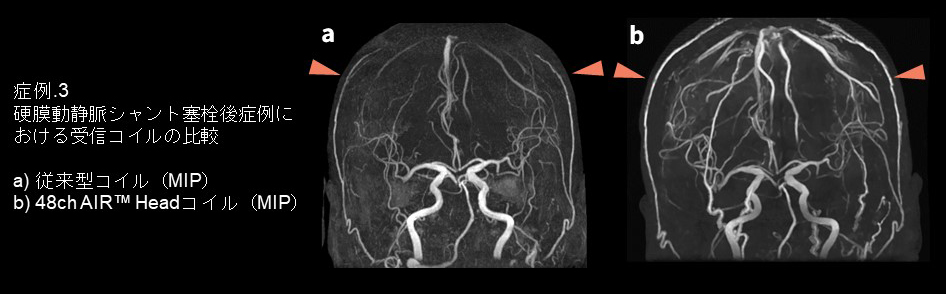

・症例3

硬膜動静脈シャント塞栓後の症例です。硬膜動静脈シャントはfeeder(外頚動脈系から供給されることが多い)の評価と、シャントポイントの特定、皮質静脈逆流の評価がそれぞれ重要であり、MRアンギオでは頭頂部を含めた広範囲の撮像が求められます。頭頂部において上段の48ch AIR™ Headコイル で撮像した方が従来型コイル よりも浅側頭動脈の描出が良好なことが分かります。